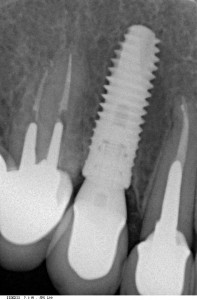

Вот пример:

![]() Контрольный снимок через 2.5 года после имплантации. Мы видим отсутствие изменений в окружающей имплантат костной ткани — верный признак качественного лечения. Мы можем быть уверены, что такой имплантат не причинит неудобств до конца жизни. |

Обратите внимание на состояние костной ткани вокруг импланта — между двумя последними снимками нет разницы. И, если убыли костной ткани не произошло за полтора года, не будет ее и далее. Следовательно, такие имплантат и коронка простоят без проблем еще 40-50 лет. Вот это я называю качественным имплантологическим лечением.